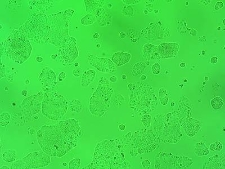

Linia komórkowa Caco-2 jest unieśmiertelnioną linią komórkową gruczolaków ludzkiego jelita grubego. Zdjęcie zostało wykonane przy użyciu odwróconej mikroskopii fluorescencyjnej (powiększenie: 10x) ; Praca nadesłana na 3nd Microscopic Art Non-Limited International Annual Contest MANIAC 2021 ; click here to follow the link